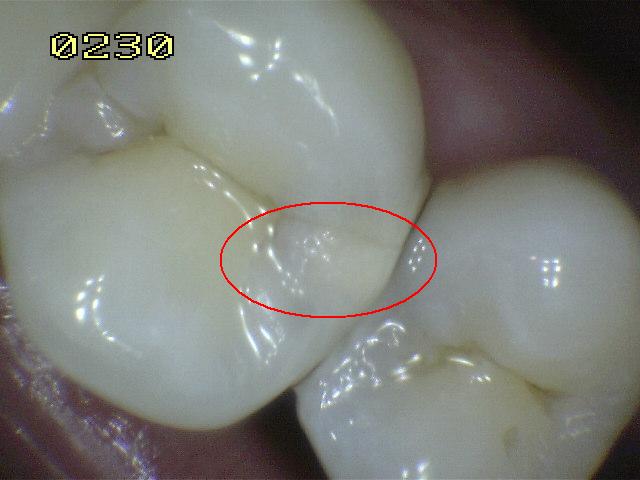

Código 1

(Caries Inicial): Primer cambio

visible en el esmalte seco. |